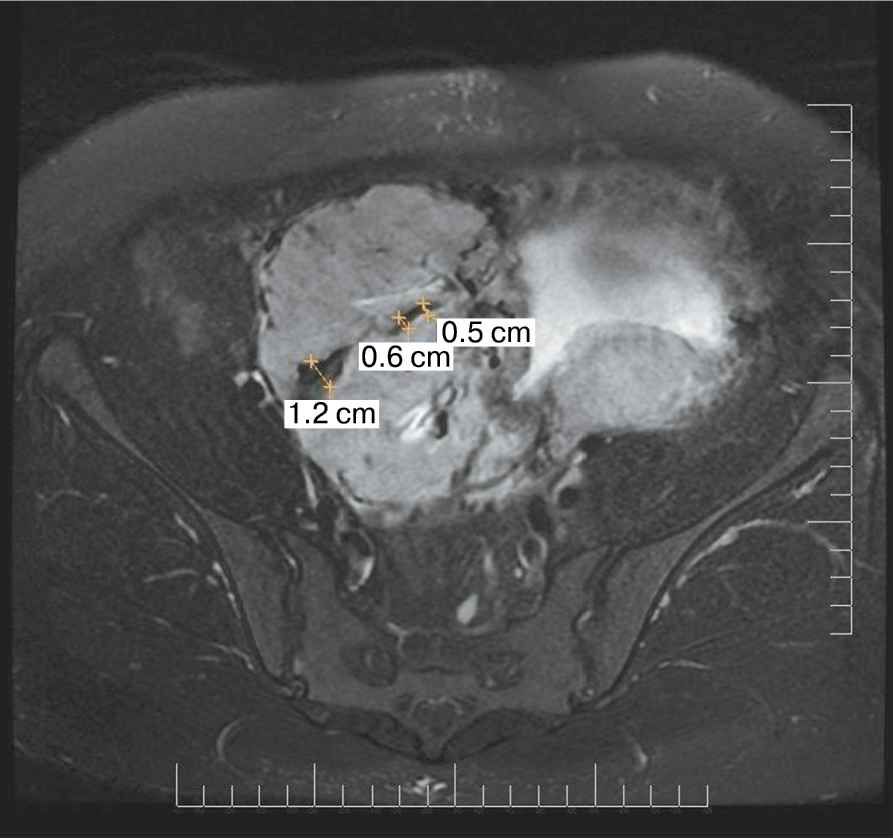

Дополнительный интерес в прогностическом плане вызывает симптом «обнаженного сосуда», представляющий собой хотя бы 1 линейную структуру диметром 5 мм и длиной около 2 см. Сама по себе гиперваскуляризация – признак при МРТ, имеющий специфичность до 80%; значения чувствительности колеблются от 42 до 69% [14]. При макроскопическом исследовании выявляется сеть субхорионических ветвистых стволовых сосудистых структур диаметром 3–5 мм, длиной 2–8 см [15]. Свое название они получили ввиду того, что минимально окружены тканями хориона и, проникая через толщу плаценты, давали минимальное количество ветвей. Dighe M. из Вашингтона опубликовала сходные данные о значимости диаметра внутриплацентарной сосудистой сети плода в прогнозе врастания плаценты; диаметр сосуда 2 мм или более часто встречался при наличии PAS, тогда как диаметр сосуда 3 мм или более был ассоциирован с более глубокой степенью инвазии и риском перипортальных кровотечений [16].

Также было отмечено наличие особых диагностических находок, таких как «мостовидные» сосуды, представляющие собой перпендикулярные сосуды на границе плаценты с миометрием, и симптом «обнаженного» сосуда – сосуд диаметром 3–4 мм длиной более 2 см, не дающий на своем пути коллатеральных веток (табл. 1).

Также стоит выделить особый тип плацентарной гиперваскуляризации, а именно включение в плацентарной ткани изменений по типу «обнаженного сосуда» (рис. 1, 2). Мы провели анализ встречаемости данного признака среди наших пациентов. Любопытным наблюдением явилось то, что данный симптом в нашей выборке встречался только при наличии placenta percreta – 6 случаев, а именно при поражении параметриев, и не встречался при плацентарной инвазии, ограниченной миометрием. «Мостовидные сосуды» были менее специфичны, тем не менее, их наличие также сопровождало тяжелые формы врастания, обусловленные более глубокой инвазией ворсин хориона, – 8 случаев.

Является ли симптом «обнаженного сосуда» патогномоничным для параметральной инвазии или нет, еще предстоит выяснить; однако в ходе исследования установлена его связь с частотой гистерэктомий в группах с наличием симптома «обнаженного сосуда», что, вероятно, обусловлено мощной сосудистой сетью коллатералей и неоангиогенезом. Во всех случаях обнаружения данного признака впоследствии была выполнена вынужденная гистерэктомия (рис. 3–6, пациентка Н., 37 лет).